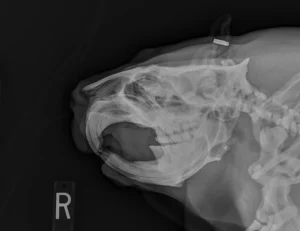

The lengthy skulls of anteaters may seem disproportionately long compared to their bodies but are an incredible adaptation when it comes to snarfing ants! Anteaters’ toothless jaws allow them to effectively hoover an abundance of ants and termites through their tube-shaped mouths. The skull also houses a very long tongue which the anteater can extend to seize insects.